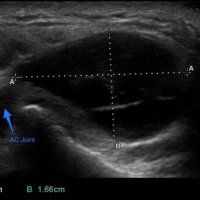

On physical examination, an AC joint cyst is a palpable fluid-filled mass. MRI scanning or a shoulder arthrogram should be obtained to evaluate the shoulder. Unenhanced MRI scans showing a large rotator cuff tear, a degenerated AC joint, and a large subcutaneous cyst adjacent to the AC joint is virtually patognomonic for the disease. Contrast administration on MR arthrogram will show the synovial fluid or intra-articular contrast extravasates from the glenohumeral joint into the subacromial bursa, into the AC joint, and then into an overlying cystic mass when a full-thickness rotator cuff tear is present, resembling a geyser spouting upwards.